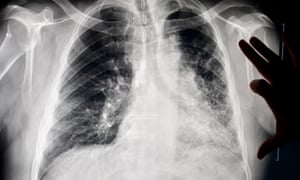

A chest x-ray in the office of Dr Brandon Crum in Pikeville, Kentucky. Photograph: Jeff Swensen/Jeff Swensen for The Guardian